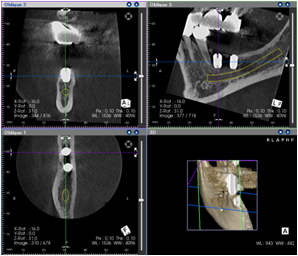

当院ではCTを完備することにより、高精度の診査、診断が可能となりました。

3次元での診断により、従来のエックス線では難しかった、口腔内の重要な組織や血管・神経の

正確な位置が把握でき、インプラント治療におけるリスクを最大限回避することが出来ます。

また、医院内に完備することにより、外部に依頼せずともCT撮影が可能となり術前診断のみならず、

必要に応じて術中、術後の撮影も可能となり、より安全にインプラント治療をご提供することが出来ます。